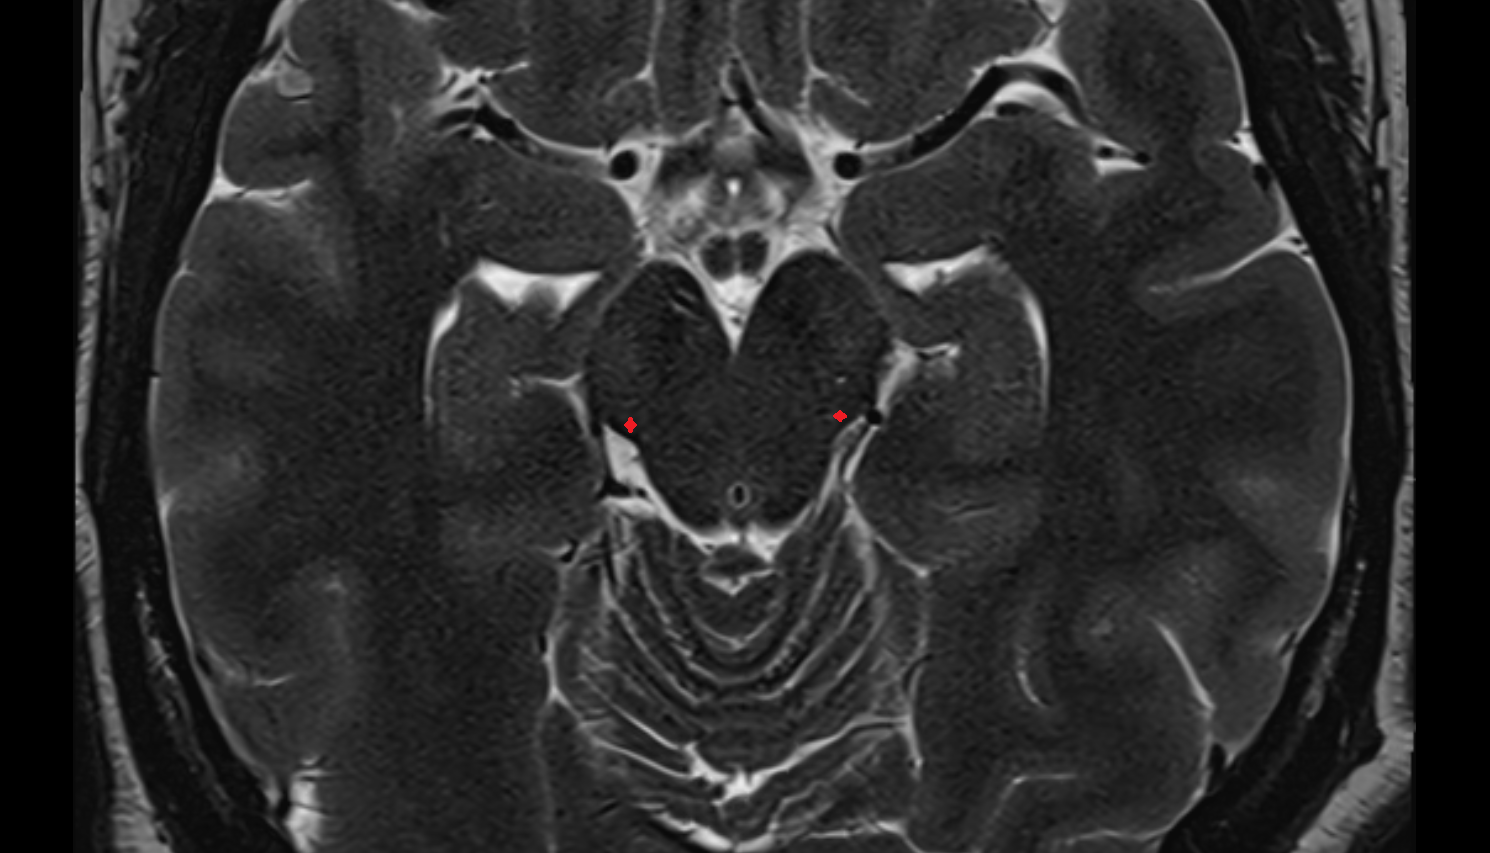

- Lateral aperture of fourth ventricle (foramen of Luschka)